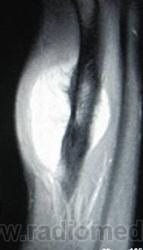

Рентгенологически обнаруживается преимущественно диафизарная локализация; прилежащий к опухоли кортикальный слой утолщен; костномозговой канала не вовлечён эндостальная поверхность кортикальной кости не изменена. Края минерализованной порции опухоли нерегулярной формы и иногда формируют радиально расположенные по отношению к оси кости, спикулы.

Рентгенологическая картина выявляет очаг поражения на поверхности кости. Очаговые фокусы кальциноза, формирование спикул, нечеткая граница опухолевого узла, мягкотканный компонент, отсутствие поражения медуллярного отдела кости, все названные рентгенологические признаки характерны для периостальной остеосаркомы. Для выявления характера поражения костномозгового канала проводится дополнительное исследование с применением КТ и МТР.